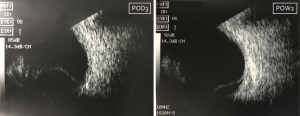

Appositional hemorrhagic choroidal detachments in two patients. In both patients, these images were captured at a follow-up visit after surgical repair of a traumatic globe injury. Left: B-scan US performed on an elderly female with hemorrhagic choroidal detachment. Right: B-scan US performed on a young male with hemorrhagic choroidal detachment.